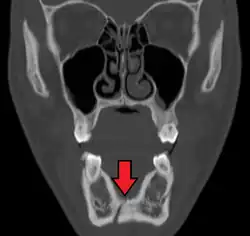

Plain film radiography

Traditionally, plain films of the mandible would be exposed but had lower sensitivity and specificity owing to overlap of structures. Views included AP (for parasymphsis), lateral oblique (body, ramus, angle, coronoid process) and Towne's (condyle) views. Condylar fractures can be especially difficult to identify, depending on the direction of condylar displacement or dislocation so multiple views of it are usually examined with two views at perpendicular angles.[11]

Panoramic radiography

Panoramic radiographs are tomograms where the mandible is in the focal trough and show a flat image of the mandible. Because the curve of the mandible appears in a 2-dimensional image, fractures are easier to spot leading to an accuracy similar to CT except in the condyle region. In addition, broken, missing or malaligned teeth can often be appreciated on a panoramic image which is frequently lost in plain films. Medial/lateral displacement of the fracture segments and especially the condyle are difficult to gauge so the view is sometimes augmented with plain film radiography or computed tomography for more complex mandible fractures.

Computed tomography

Computed tomography is the most sensitive and specific of the imaging techniques. The facial bones can be visualized as slices through the skeletal in either the axial, coronal or sagittal planes. Images can be reconstructed into a 3-dimensional view, to give a better sense of the displacement of various fragments. 3D reconstruction, however, can mask smaller fractures owing to volume averaging, scatter artifact and surrounding structures simply blocking the view of underlying areas.

Research has shown that panoramic radiography is similar to computed tomography in its diagnostic accuracy for mandible fractures and both are more accurate than plain film radiograph.[12] The indications to use CT for mandible fracture vary by region, but it does not seem to add to diagnosis or treatment planning except for comminuted or avulsive type fractures,[13] although, there is better clinician agreement on the location and absence of fractures with CT compared to panoramic radiography.[14]

Panoramic radiograph of a simple mandible fracture of the right mandibular body, minimally displaced. Note that the teeth to the left of the fracture do not touch -

lateral oblique image demonstrating a fractured mandible.

Towne's view of a bilateral condyle fracture. White arrow is a fracture on the neck of the condyle. Black arrow shows the condyle pulled to the medial. The same injury can be seen on the opposite side -

3D CT reconstruction of mandible fracture, white arrow marks fracture, red arrow marks moderate displacement and open bite -

occlusal radiograph of a mandibular parasymphysis fracture